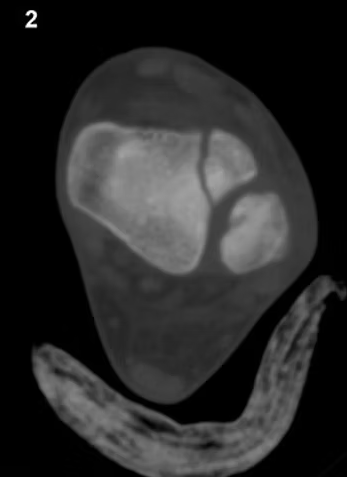

• Nota: A Tomografia Computadorizada (TC) é padrão-ouro para fraturas articulares (platô tibial, pilão tibial) e do esqueleto axial.

Reconstrução tomográfica do tornozelo com a técnica MPR no plano coronal (de anterior para posterior). Fonte: https://www.mskrad.com.br/post/fratura-de-tillaux-juvenil

Reconstrução tomográfica da tíbia distal com a técnica MPR no plano transversal. Fonte: https://www.mskrad.com.br/post/fratura-de-tillaux-juvenil